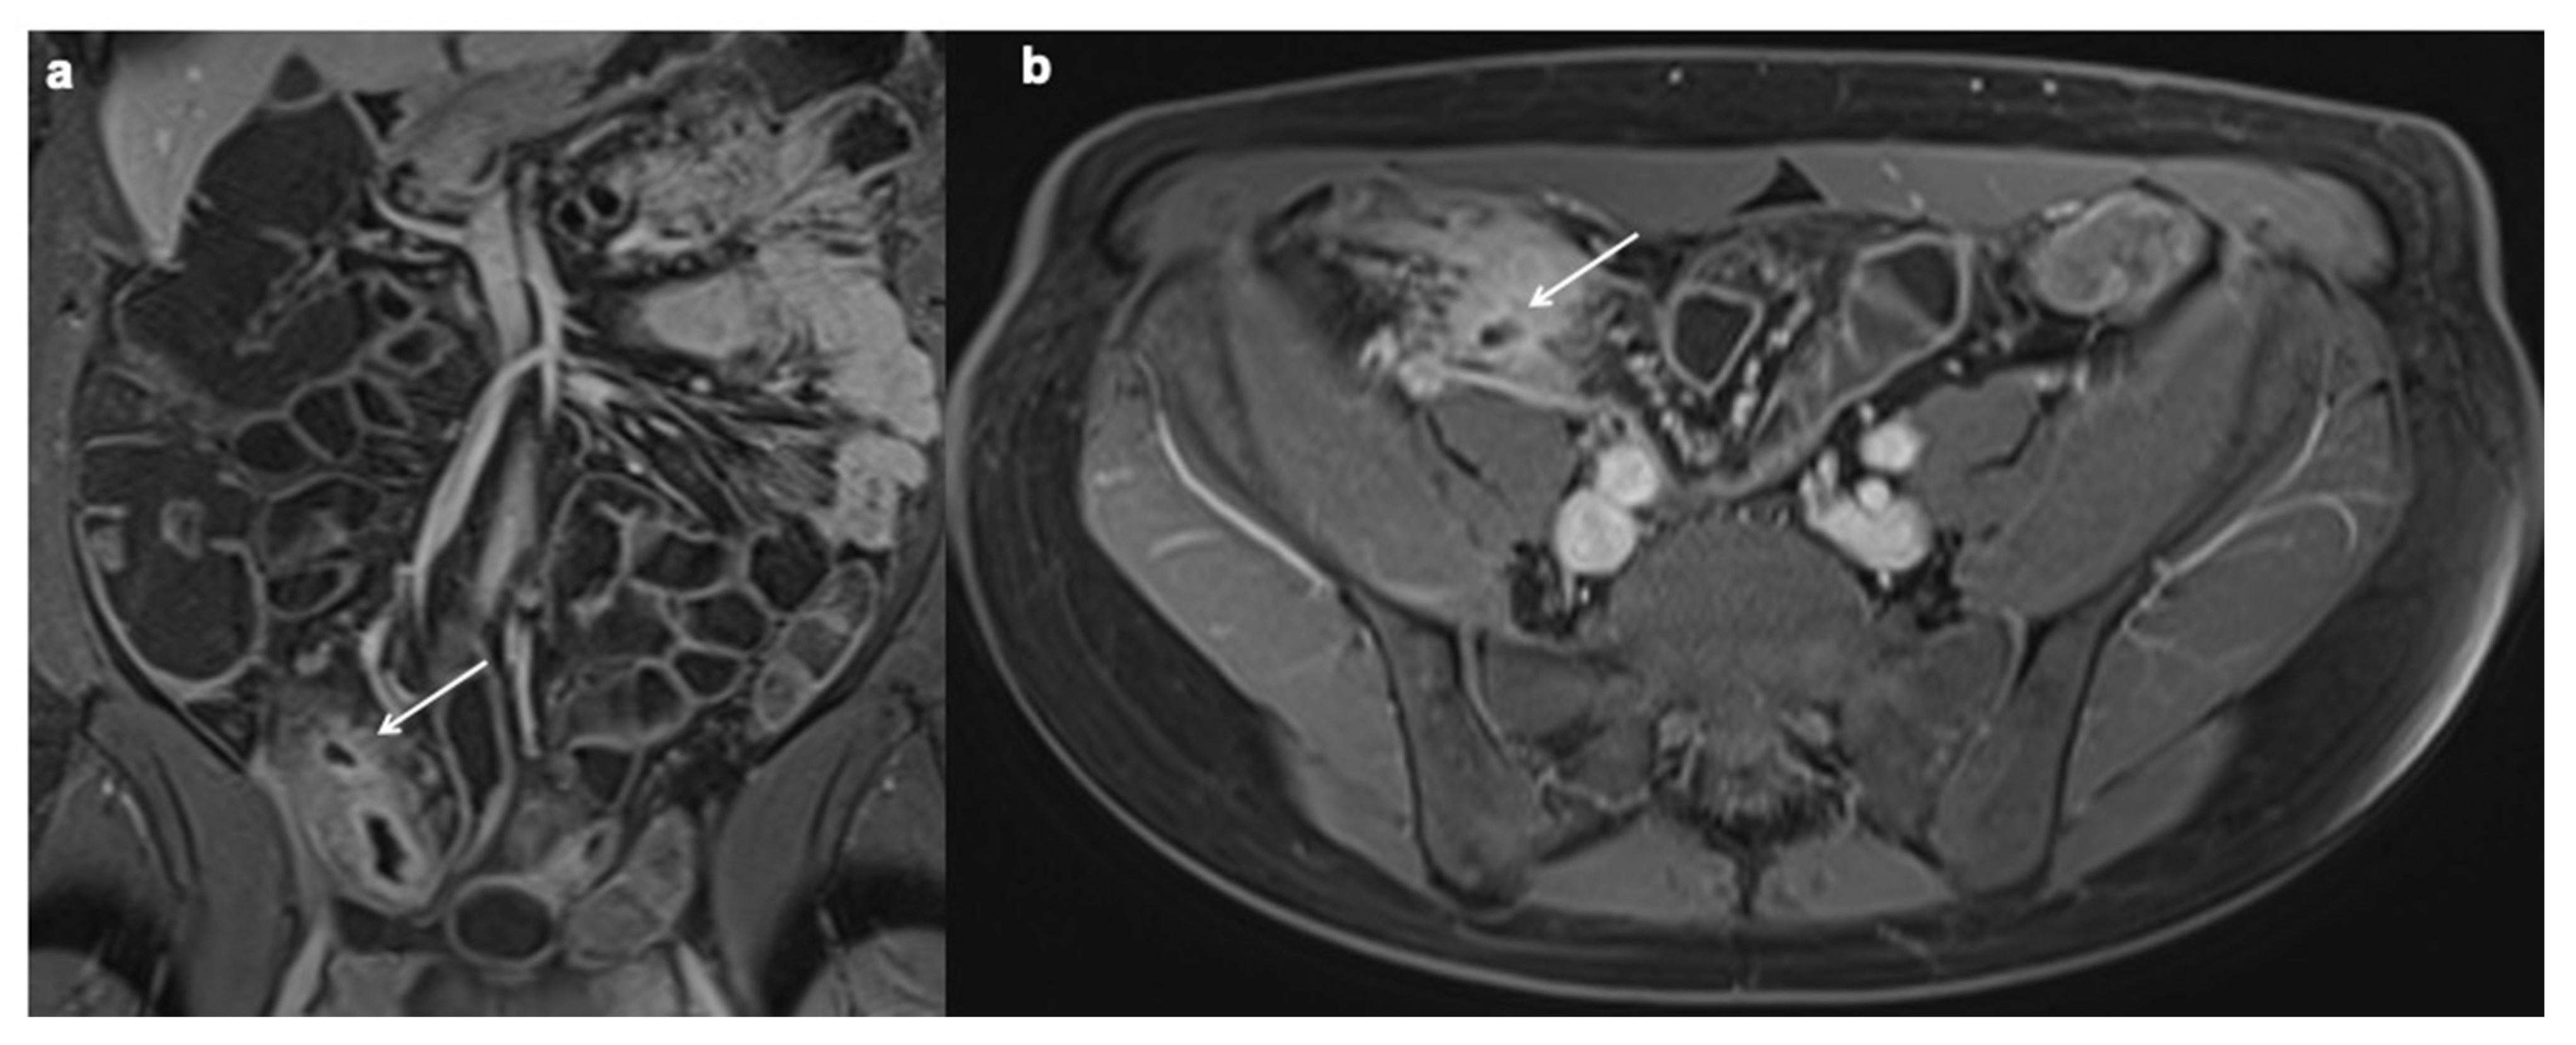

11. Imaging Findings Associated with Penetrating CD Inflammation and Complications

12. Imaging Findings Associated with Non-Active CD Inflammation